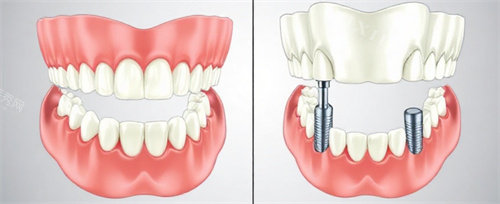

三、种植牙实例实测,结果说话

为了让大家更直观感受丽如口腔的种植牙技术,下面分享一位患者的真实经历。患者李先生,因牙齿意外脱落,严峻影响了日常生活和饮食。在多方打听和对比后,他选择了丽如口腔。

在初诊时,医生团队为李先生进行了齐全细致的口腔检查,包括口腔 CT 扫描等,详细了解其牙槽骨状况、邻牙情况等,随后根据他的实际情况制定了个性化的种植牙方案。在种植手术过程中,李先生表示医生操作熟练、手法轻柔,整个过程没有明显的疼痛感,原本紧张的心情也逐渐放松下来。

术后,李先生按照医生的嘱咐进行护理,定期复诊。经过一段时间的改善,种植牙与牙槽骨理想结合,使用起来和真牙几乎无异,无论是咀嚼功能还是美观度都令他十分满意。李先生直言:“选择丽如口腔做种植牙是正确的决定,医生技术好,服务也贴心,让我重新找回了自信的笑容。” 从李先生的实例可以看出,丽如口腔在种植牙技术方面具备扎实的正规能力和丰富的临床经验,能够为患者带来理想的治疗结果。